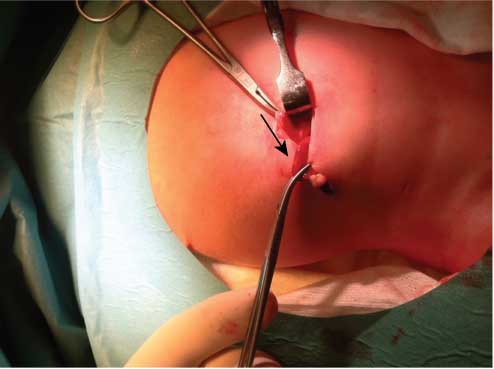

A female infant was born at 36 weeks of gestation to a 30-year-old woman by spontaneous vaginal delivery. The mother was positive for Streptococcus group B and received adequate intrapartum chemoprophylaxis with ampicillin. She had no signs of chorioamnionitis. The APGAR scores were 9, 10 and 10 at 1, 5 and 10 min, respectively. The birth weight was 2760 g. The baby was admitted at 2 h of life due to hypoglycemia (35 mg/dL) and poor feeding. Intravenous fluids containing glucose at 4.5 mg/kg per minute were initiated, with an increase in glucose levels to more than 60 mg/dL. She presented no subsequent episodes of hypoglycemia and started enteral feeding with formula. Whole blood examination and C reactive protein (CRP) on admission were normal. On the second day of life, the infant appeared to be uncomfortable and presented with bloody stools and bile-stained gastric aspirate. Whole blood analysis, CRP and routine coagulation tests were repeated, revealing no abnormalities. Abdominal X-ray showed signs of suspected obstruction, and the abdominal ultrasound revealed a small quantity of free abdominal fluid. Antibiotics (ampicillin and gentamicin) were started. The infant continued to pass bloody stools, bile-stained and bloody gastric aspirate, and abdominal distension. On day 3, she presented with leukopenia of 2700/mm3 (neutrophils 50%) and platelet count of 144,000/mm3. CRP increased to a maximum of 63 mg/L. At this point metronidazole was added. Abdominal ultrasound revealed an increase in free abdominal fluid compared with the previous examination; the mesenteric vein/mesenteric artery ratio was preserved. Abdominal X-ray showed a fixed loop, outlining a whirlpool sign, and no signs of intestinal pneumatosis (Figure 1). A diagnostic laparoscopy was performed. A 5-mm supraumbilical port was inserted. This procedure showed good intestinal vascularization, slight delegate distension and normal colon. Then 3-mm instruments were inserted under direct vision via stab incisions, enabling identification of generalized peritonitis secondary to inflammatory process in the right iliac fossa, likely to be appendicitis. Laparoscopic appendectomy was performed (Figure 2). There were no intraoperative complications, and the infant had a good postoperative recovery. She received regular paracetamol for pain relief and did not require morphine. The patient started feeding 3 days after surgery and received full feeds by the fifth postoperative day. She was treated with antibiotics for 10 days and discharged at day 9 postoperatively.

Intraoperative photograph of the appendix (arrow).

Histologic examination of the appendix showed that the lumen was filled with concretions with dense fibrinosuppurative infiltrate and transmural granulation at the site of perforation. Follow-up showed no signs of underlying disease.